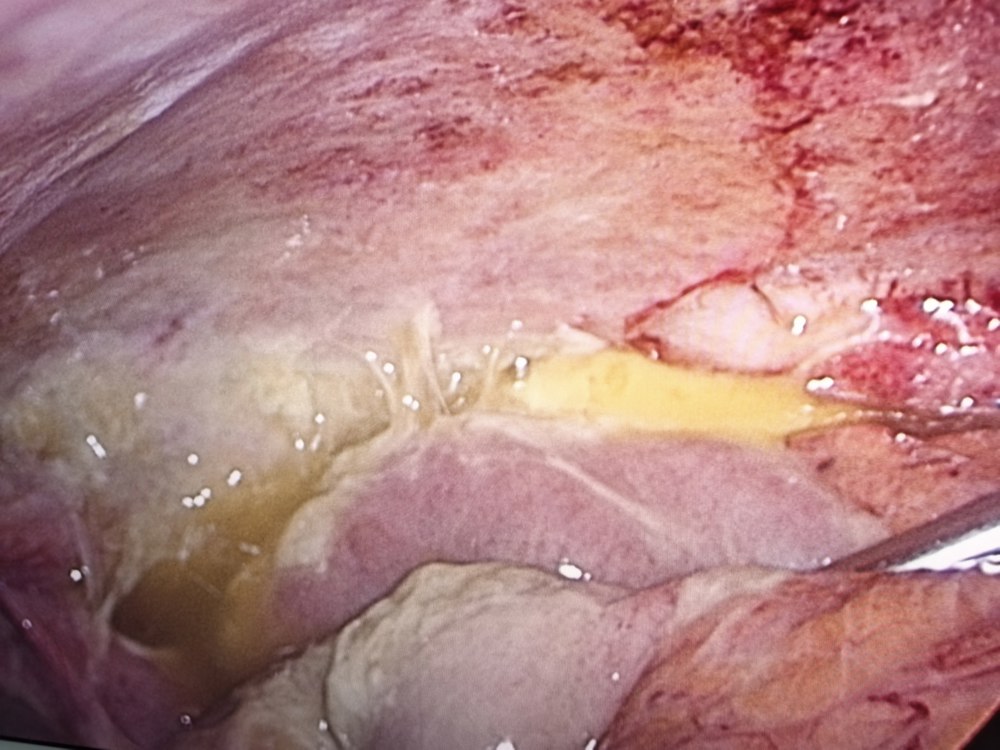

在麻醉科与手术室的密切配合下,金根标带领手术团队为患者实施剖腹探查。术中发现患者小肠系膜多处撕裂、肠管存在两处穿孔,腹腔内有大量消化液及食物残渣,污染严重。手术团队迅速清除腹腔污染物,仔细修补肠管破口,并行腹腔冲洗和引流,手术过程顺利。